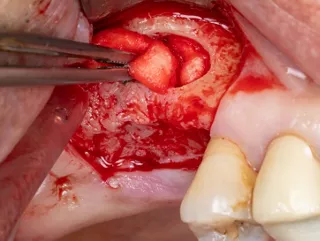

3. Flap detachment:

Crestal incision and diverging vertical discharges. Mucoperiosteal lift.

4. Sinus window : Subtractive osteotomy without preservation of the bone flap using a 2.5 mm diamond bur mounted on a surgical handpiece. The Schneiderian membrane (sinus mucosa) of slightly bluish grey color is exposed.

5. Initiation of lifting of the sinus mucosa through the inferior mesial window angle.